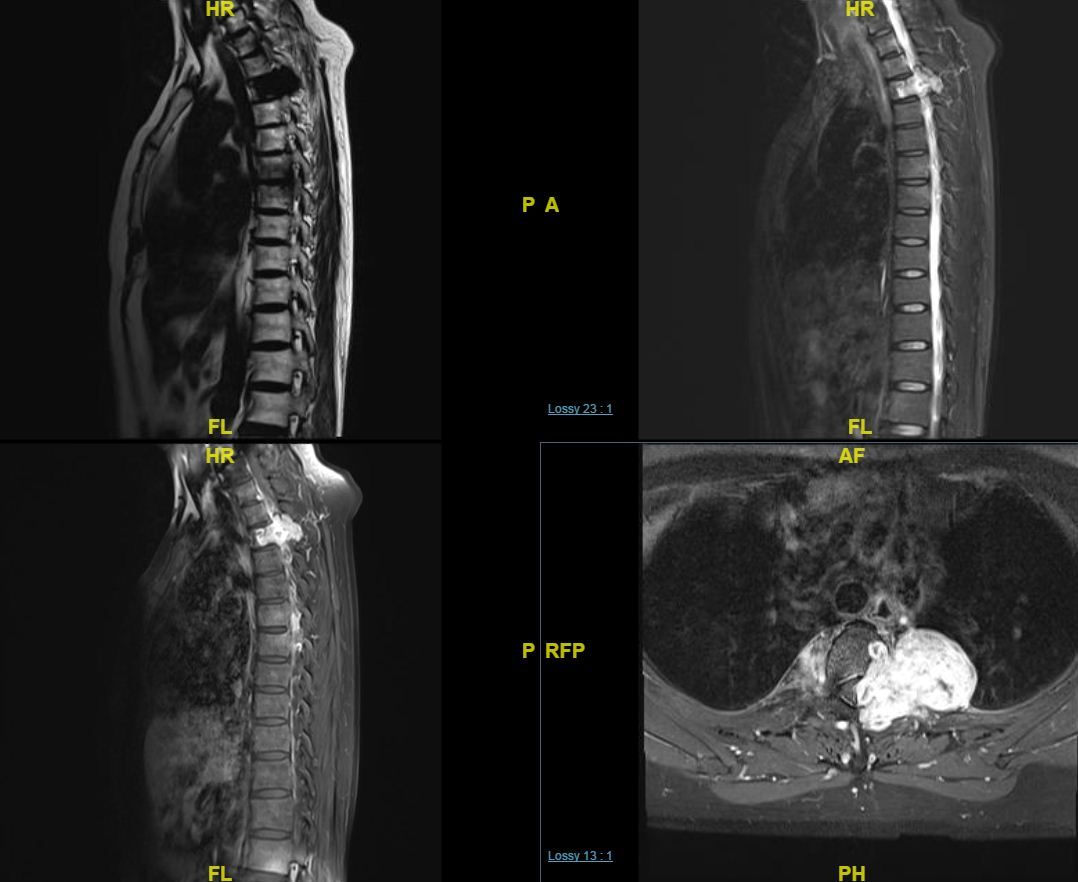

胸椎旁神经鞘瘤t11